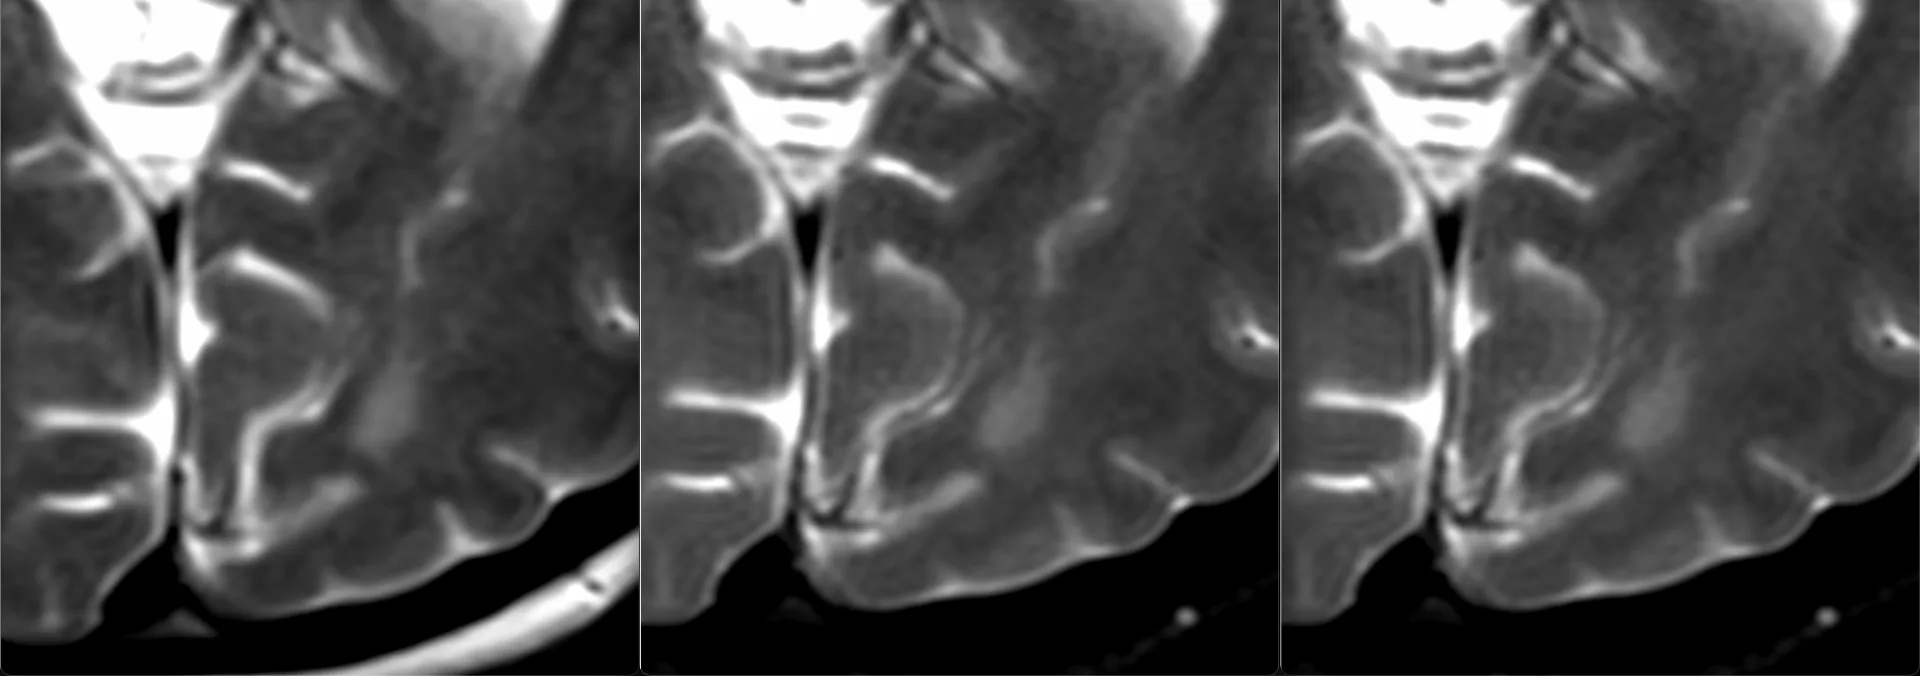

Женщина 32 года. Больной считает себя с 2024 г, когда стала отмечать онемение угла рта. Со слов пациентки ей был предварительно выставлен диагноз - РС, но дополнительных методов обследования и специфического лечения не проводилось. В настоящее время жалоб нет. В исследовании от октября 2024 отмечался очаг в левой затылочной доле с выраженным контрастированием, в настоящее время этот же очаг отмечается с сохраняющимся контрастированием. Формально - есть выполнение критериев диссеминации и в пространстве (юкстакортикальный и перивентрикулярный очаги есть), и во времени (есть усиливающиеся и неусиливающиеся очаги), клиника тоже вполне укладывается. Но! Найти в литературе подобных случаев мне не удалось, видел сам и максимум, что находил в литературе - полгода контрастирования. Получается, мы имеем дело с крайне атипичным рассеянным склерозом, или это не рассеянный склероз. А тогда что? Сосудистая мальформация не вариант - на SWI не видать. Какая-то ганглиоглиома? А другие очаги тогда что? Есть соображения? Кстати, диффузия стойко повышенная, и на б1000 почти не видно (изо). На Т2 не меняется